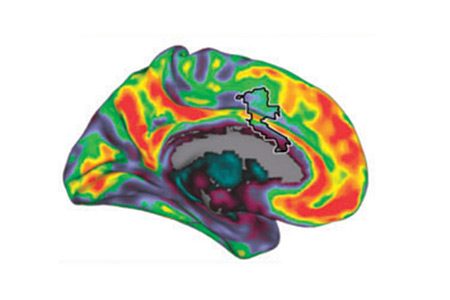

Singing in the brain: Neural representation of music and voice as revealed by fMRI

Vocal and musical stimuli elicit preferred responses from different parts of the temporal lobe. These include

the superior temporal sulcus and gyrus for the former, and the planum polare and temporale for the latter.

Since singing has vocal and musical properties, it uses all of these areas.